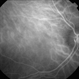

- endogenous endophthalmitis, Optos, candida endophthalmitis, ultra-wide field imaging, retinal infiltrates, left eye, scotoma, drug abuse, pseudocolor

- Ultra-wide field Optos pseudocolor image of an 45-year-old male presenting with endogenous endophthalmitis affecting his left eye. Candidiasis was at high considerations due to intravenous drug abuse and recent history of dental abscess. Patient developed a subretinal infiltrate resulting in central scotoma and responded well to anti-fungal treatment.